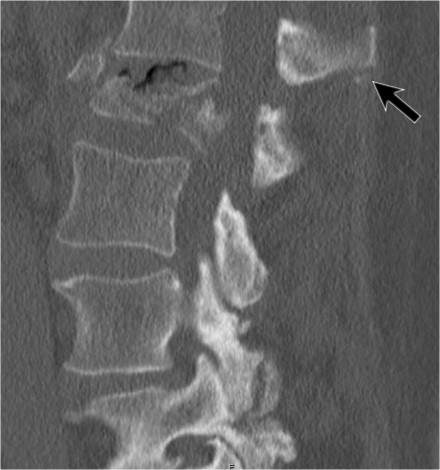

The images are of a patient with a typical bamboo spine as a result of ankylosing spondylitis.

After a fall on his back no fracture was seen on the x-rays.

However the CT shows a thin fracture line through the anterior side of the vertebral body and also through the spinous process.